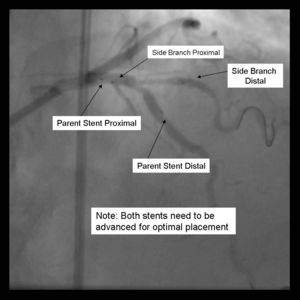

4) The 2nd stent is advanced into the parent vessel. This is also placed beyond the intended deployment site.

5) The side branch stent is pulled back into the parent vessel about 5 mm. This ensures adequate coverage of the ostium.

6) The parent stent is pulled back crossing the side branch and the proximal end is placed proximal to the proximal end of the side branch stent.